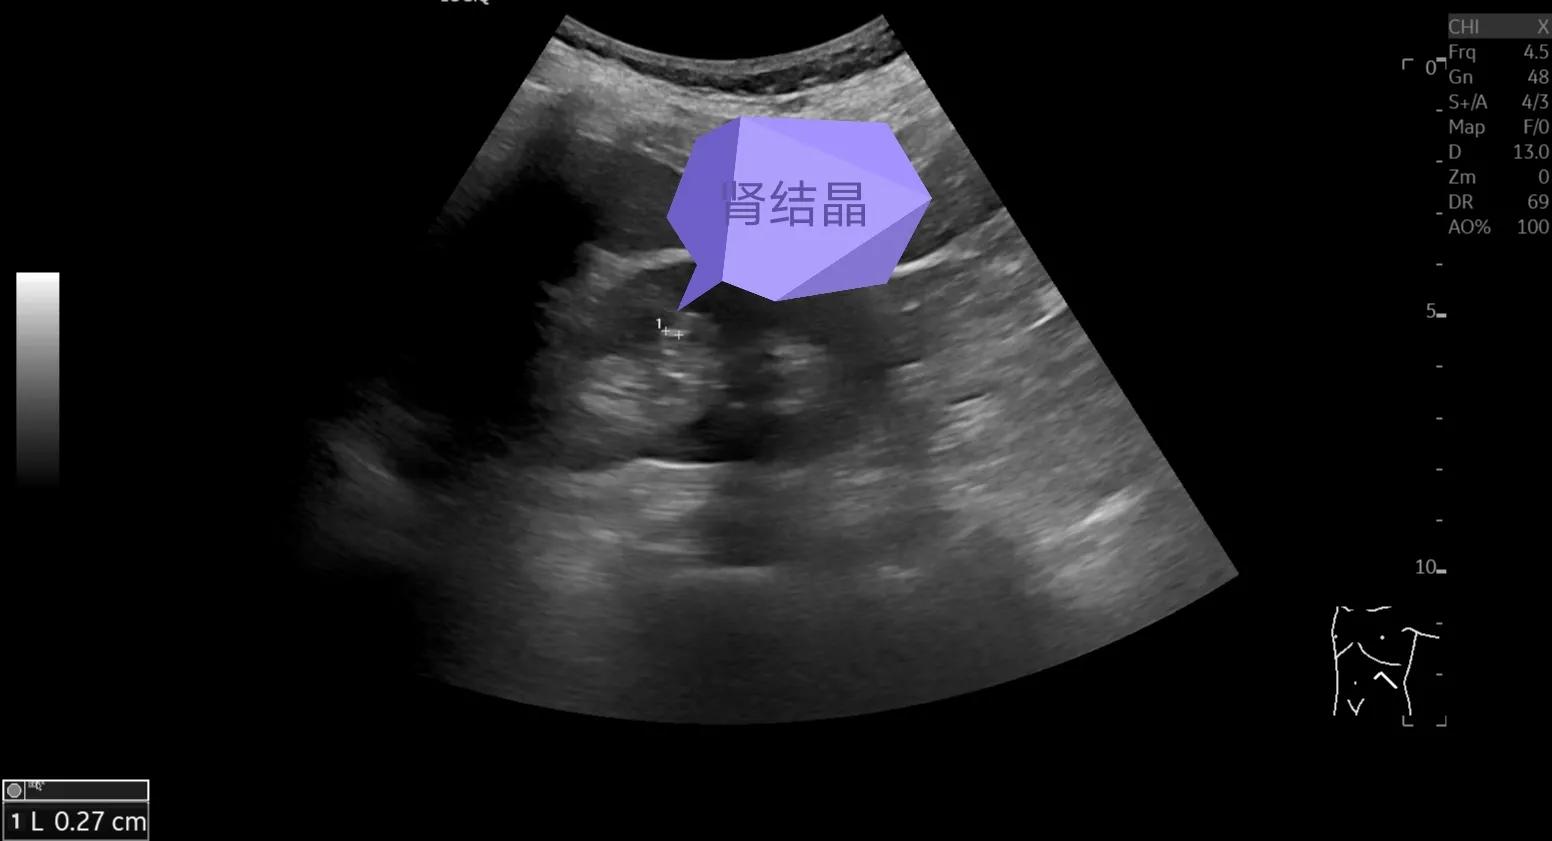

图中剪头所示那个亮亮的结构,强回声斑块便是结晶,直径2.7mm